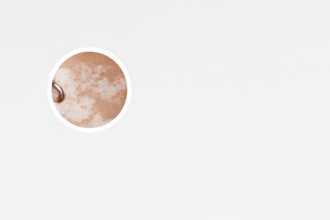

白癜風(fēng),其醫(yī)學(xué)特征為皮膚上出現(xiàn)不同大小的白斑。在治療白癜風(fēng)的過程中,有時會出現(xiàn)白癜風(fēng)邊緣不清晰的情況,給患者帶來困擾。本文將從多個角度討論白癜風(fēng)治療中邊緣不清晰的問題,幫助患者更好地理解和處理這一情況。

白癜風(fēng),其特點(diǎn)是局部皮膚失去色素,形成白斑。治療白癜風(fēng)的過程中,有時候會遇到邊緣不清晰的情況,這給患者帶來了困擾。下面,我們從多個角度來討論白癜風(fēng)治療中邊緣不清晰的問題,給患者一些有用的建議。